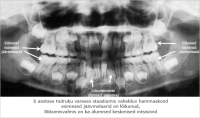

röntgenpilt

vahelduv hammaskond